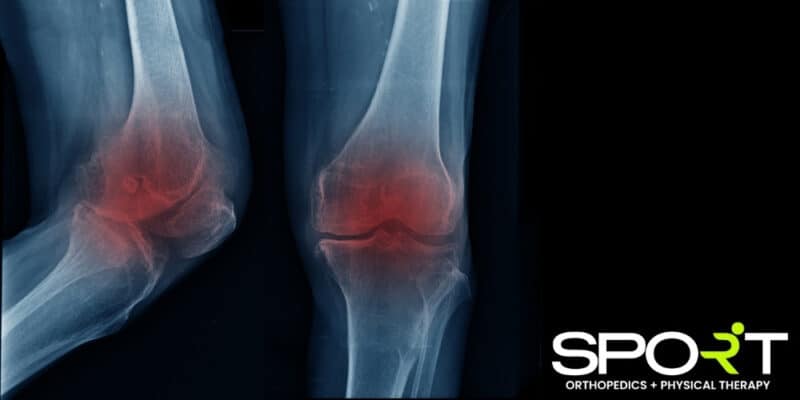

What Is Knee Arthritis?

When the knee joint suffers inflammation and a breakdown of the cartilage that cushions the knee, this is known as knee arthritis. Arthritis in any joint in the body can cause joint pain, joint stiffness, swelling, and even a grating sensation between the bones. As soon as you experience arthritis of the knee, we recommend speaking with a knee specialist. The longer you wait to treat the problem, the more the knee joint gradually wears down and causes pain.

We will also order imaging tests, such as X-rays, to get a visual of how much cartilage loss you currently have. Additionally, we may draw out fluid from the joint capsule, which is a process known as joint aspiration. Testing this fluid can help your doctor gain a better understanding of the source of your pain.